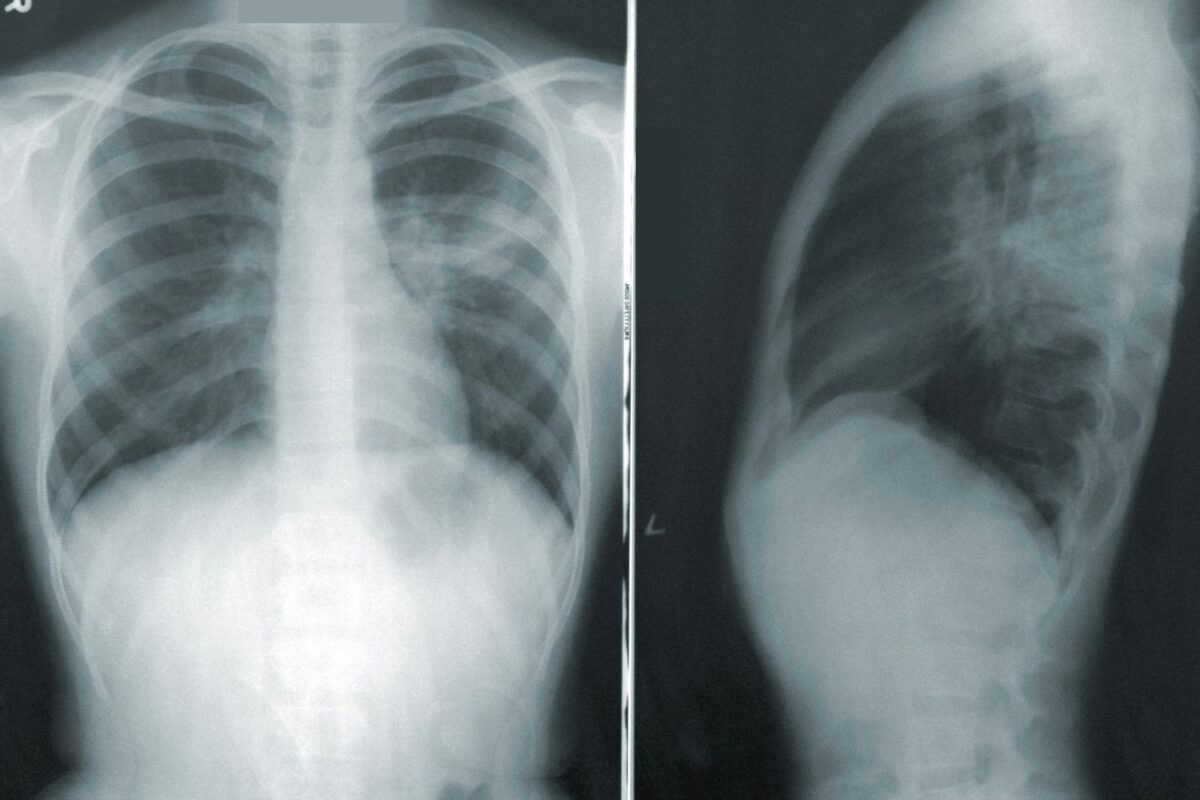

Por otro lado, se puede confirmar el resultado con radiografía de tórax, ya que permite poder observar la inflamación en los pulmones.